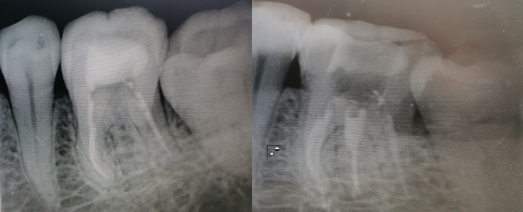

患者,女,48岁。主诉:“左下后牙咬合痛5天。”

36(牙合)面见白色充填物良好,冷热诊迟缓性痛,叩(+),无松动

X线检查:(牙合)面高密度影近近中髓角,牙根完整,未见根内、根外吸收

诊断:36慢性牙髓炎

治疗计划:根管治疗术+冠修复